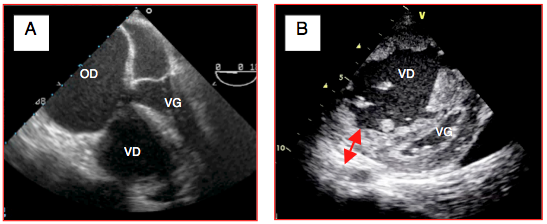

Figure 27.81 : Embolie pulmonaire. A: thrombus dans l'OD (flèche); dilatation massive du VD, le VG est comprimé, l'apex est formé par le VD. B: thrombus en transit dans l'OD. C: thrombus dans l'AP droite; cette image n'est pas toujours visible. D: thrombus enclavé dans un foramen ovale perméable et prêt à basculer dans l'OG (flèche rouge).

Figure 27.82 : Défaillance droite sur embolie pulmonaire. A: embolie pulmonaire aiguë; le VD et l'OD sont dilatés et empiètent sur les cavités gauches. B: dilatation et hypertrophie massive du VD sur hypertension pulmonaire due à des embolies récédivantes; la paroi du VD mesure 1.8 cm d'épaisseur (vue court-axe transgastrique).